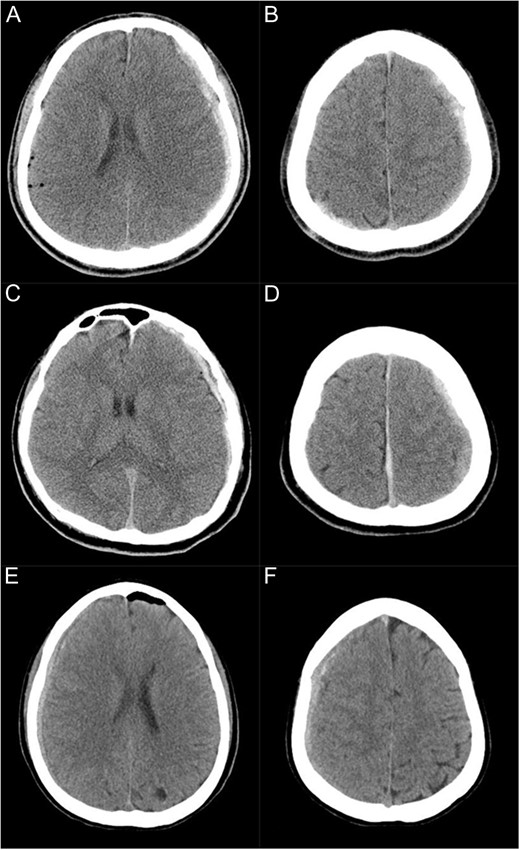

CT scans immediately after the surgery showing subdural haematoma in three cases (A and B: Case 1, C and D: Case 2, E and F: Case 3). (A and B) Subdural haematoma is present on the left supratentorial convexity as well as in the parieto-occipital area on the right side. (C and D) Subdural haematoma is present on the left supratentorial convexity and along the falx. (E and F) Subdural haematoma is present on the right supratentorial convexity.